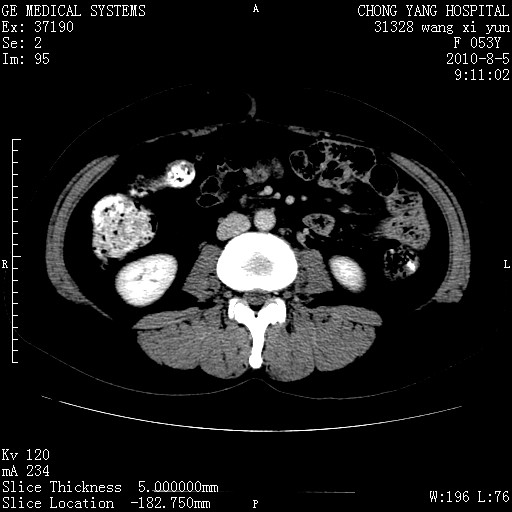

标题: CT28214:F41Y 血尿二十天,建议盆腔平扫加增强。

1)考虑肝左叶胆管细胞癌。2)脂肪肝。